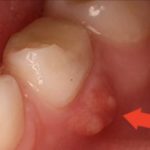

Лечение всегда направлено на то, чтобы спасти зубы, избежав их удаления. Поэтому первоочередная задача – удалить чирий с гнойным содержимым. Пытаться сделать это самостоятельно не рекомендуется, поскольку неграмотная обработка ранки вызовет распространение болезни. Также не стоит надеяться, что прыщик прорвет, и этим все закончится. Попадая в организм, гной вызывает тяжелые патологии внутренних органов. Прежде всего, страдает желудок, печень. Поэтому удаление гноя и разработкой курса лечения должен заниматься только врач.

Чирий и другие гнойные образования не рекомендуется лечить спиртовыми компрессами или нагретым маслом, если это не согласовано со стоматологом, поскольку от этого воспаление может только усилиться. На все время восстановления необходимо отказаться от жесткой пищи, щеток с грубой щетиной, отбеливающих паст. Употреблять алкоголь также не следует, чтобы не вызвать рецидив из-за раздражения слизистой области.